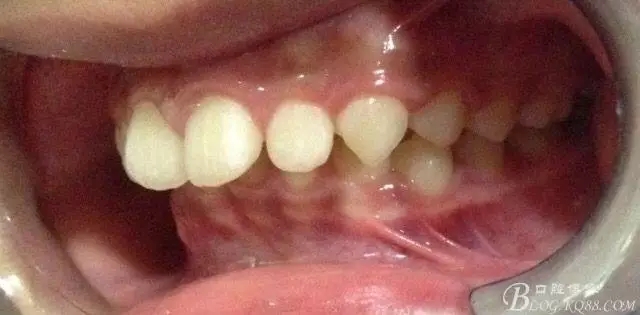

看看口內(nèi)照吧!真象“大暴牙”v假象“大暴牙”

三度深覆合,三度深覆蓋,尖牙,磨牙均二類關(guān)系!